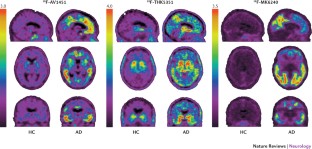

Villemagne, V. L., Fodero-Tavoletti, M. T., Masters, C. L. & Rowe, C. C. Tau imaging: early progress and future directions. Lancet Neurol. 14, 114–124 (2015).

Maruyama, M. et al. Imaging of tau pathology in a tauopathy mouse model and in Alzheimer patients compared to normal controls. Neuron 79, 1094–1108 (2013).

Walji, A. M. et al. Discovery of 6-(Fluoro-(18)F)-3-(1H-pyrrolo[2,3-c]pyridin-1-yl)isoquinolin-5-amine ([18F]-MK-6240): a positron emission tomography (PET) imaging agent for quantification of neurofibrillary tangles (NFTs). J. Med. Chem. 59, 4778–4789 (2016).

Okamura, N. et al. Characterization of [18F]THK-5351, a novel PET tracer for imaging tau pathology in Alzheimer's disease. Eur. J. Nucl. Med. Mol. Imag. 41, S260 (2014).